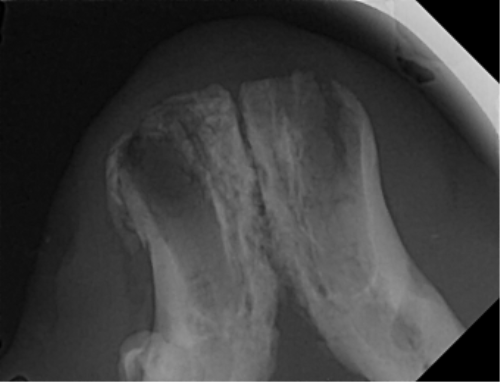

| 치료과정 | -다행히 상추는 금세 포획이 되어서 2번 시도 만에 병원으로 데려갈 수 있었습니다. -많이 마르고 구내염이 꽤 지속된 상태로 보여 검사 후 수술을 진행하기로 했습니다. 방사선, 초음파, 혈액검사를 진행했고 검사상 감사하게도 수술이 가능한 수치가 나왔습니다. 더 못 먹고 염증이 지속될 경우 건강이 더 상할 것 같아 바로 수술을 진행하였습니다. -진통 패치 및 진통제, 항생제 처방을 해주시고 먹는 것을 병원에서 관찰해주셔서 소식을 전해 들을 수 있었습니다. 아이는 첫날 조금밖에 먹지 않았으나 다음날부터 습식에 비벼 준 사료 등을 두 그릇씩 먹으며 씩씩하게 지내주었습니다. 병원 케어를 좀 더 받았으면 하여 일주일 정도 입원을 하였고 피하수액 등을 하여 탈수도 교정이 좀 되었으면 하는 심정이었습니다. -병원에서 마취 상태에서 입 안 사진을 찍어 기록한 후 보여주셨는데 꽤 심각했습니다. 목구멍 쪽 증식한 염증을 많이 절제하였고 레이저 치료까지 진행하였습니다. 치아 엑스레이 촬영도 모두 보내주셔서 기록해두는 데 도움이 되었습니다. -아이가 자발 식이를 잘 할 경우 퇴원을 해도 되기에 집에서 회복 공간을 만들어주었습니다. 나가고 싶은 듯 바깥을 보며 처음에 힘들어했지만 점차 적응하며 편안하게 휴식을 했습니다. 밥은 꼬박꼬박 두 그릇 넘게 챙겨 먹었고 소화가 잘 되는 습식 위주로 주었습니다. 건사료를 언제쯤 먹을 수 있나 관찰하려 두었더니 며칠 안에 금세 먹었습니다. 알갱이 작은 사료를 주었으나 기존에 먹던 맛을 먹고 싶은지 그것만 먹었습니다. |

| 대상묘 치료중 사진 |          |